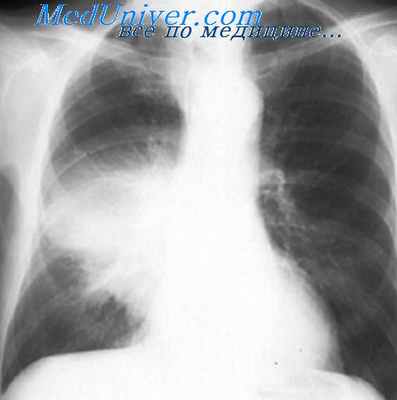

Легионеллезная пневмония начинается остро с резкого озноба, высокой температуры - до 40°С и выше, выраженной интоксикацией, прострацией, слабости, атаксии. Симптомы поражения легких проявляются в период с 4-го по 7-й день болезни. Появляются одышка, кашель, вначале он непродуктивный, затем становится сильным, со слизистой мокротой, часто с кровью. Выслушиваются влажные хрипы и шум трения плевры (В.Е. Ноников). На рентгенограммах легких отмечаются инфильтраты, часто двусторонние. У некоторых пневмония носит мигрирующий характер. Инфильтраты могут быть интерстициальными, лобарными или пятнистыми. Иногда образуются полости и абсцессы, возможны пневмонит и альвеолит.